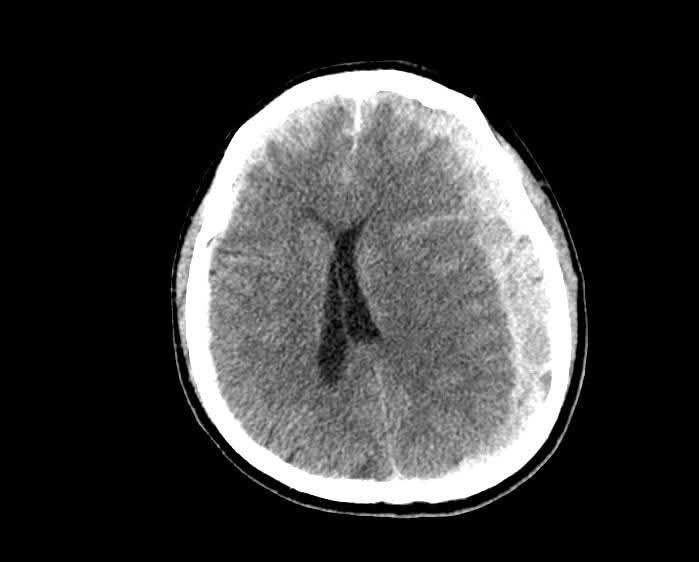

Hình ảnh máu tụ trên phim chụp - Ảnh BVCC

CT sọ não cấp cứu ghi nhận: Tụ máu dưới màng cứng hai bán cầu, bên trái dày tới 18 mm; Xuất huyết dưới nhện rải rác hai bán cầu; Đường giữa lệch 15 mm – dấu hiệu chèn ép não nghiêm trọng; Vỡ xương thái dương phải, xương đá trái, kèm tụ dịch sào bào chũm.